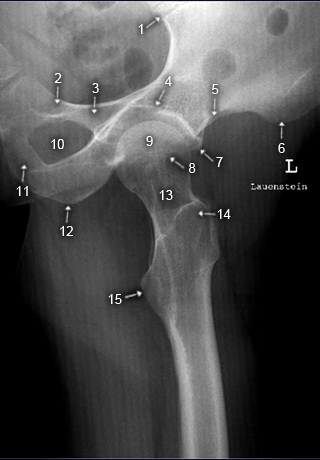

Hüfte axial nach Lauenstein

1. Articulatio sacroiliaca

2. R. superior ossis pubis

3. Corpus ossis pubis

4. Pfannengrund

5. Spina iliaca anterior inferior

6. Spina iliaca anterior superior

7. Pfannenerker

8. dorsaler Pfannenrand

9. Caput femoris

10. Foramen obturatum

11. R. inferior ossis pubis

12. Tuber ischiadicum

13. Collum femoris

14. Trochanter major

15. Trochanter minor